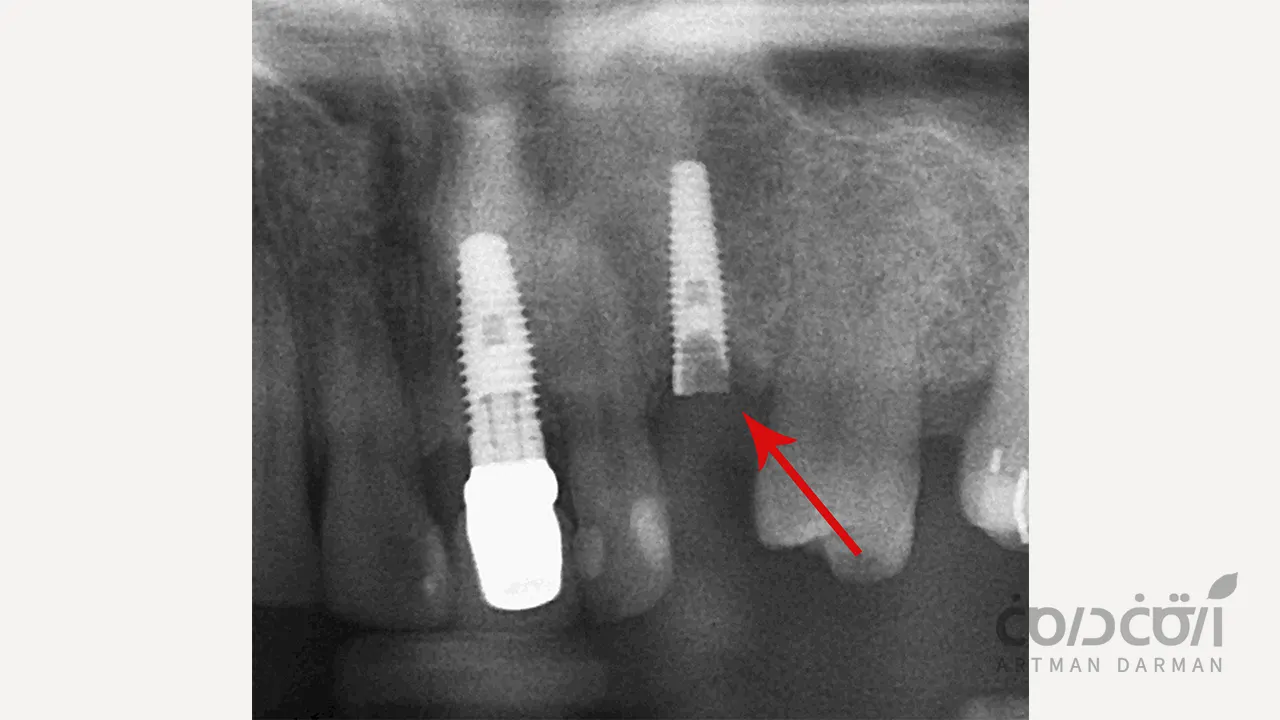

در یک شکستگی ایمپلنت دندان واقعی، خود پایه تیتانیومی که به طور کامل به استخوان جوش خورده است، دچار ترک یا شکست کامل می شود. این شکستگی معمولاً در ضعیف ترین نقطه ایمپلنت، یعنی در ناحیه گردن آن (نزدیک به محل اتصال به اباتمنت) رخ می دهد.

تشخیص قطعی توسط دندانپزشک و با استفاده از روش های زیر انجام می شود:

- معاینه بالینی: بررسی لقی غیرطبیعی پروتز.

- تهیه رادیوگرافی (X-ray): این مهم ترین ابزار تشخیصی است. در رادیوگرافی، یک خط شکست واضح در بدنه ایمپلنت قابل مشاهده است. گاهی برای بررسی دقیق تر، از اسکن سه بعدی (CBCT) استفاده می شود.